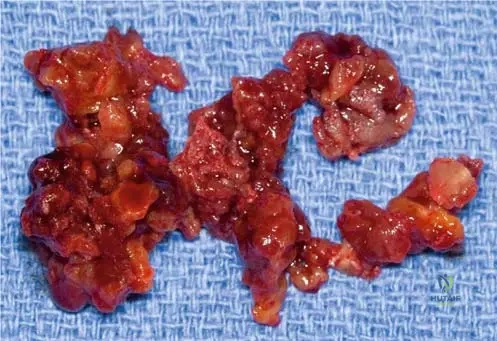

A 35-year-old female presents with mild, intermittent pain in her distal femur. Radiographs show an intramedullary lesion with some endosteal scalloping and punctate calcifications. A biopsy is performed, and the pathologist describes a hypocellular lesion with a lobular growth pattern and uniform nuclei. This histological description is consistent with which of the following?

Correct Answer: C

Rationale: The text and Fig. 8.23 describe enchondromas as having a "lobular growth pattern and hypocellular nature... The nuclei are uniform." This histological description is characteristic of a benign enchondroma, even if the lesion is painful or appears somewhat aggressive radiographically. The other options represent malignant tumors with different histological features.

A 26-year-old male undergoes biopsy of an intramedullary lesion in his proximal femur. Histological examination reveals a cartilaginous lesion with uniform nuclei. What is the significance of "uniform nuclei" in the context of this lesion?

Rationale: The text and Fig. 8.23 describe enchondromas as having "uniform nuclei," which is a histological feature of a benign lesion. Nuclear uniformity (lack of pleomorphism) is a critical indicator distinguishing benign cartilaginous lesions from malignant ones like chondrosarcoma. The other options are incorrect interpretations of this benign histological feature.

A pathologist examines a low-power histological slide of an enchondroma from a 15-year-old patient. Which characteristic growth pattern would be most evident?

Rationale: The clinical context for Fig. 8.23 a, b explicitly states, "Low-power images demonstrate the lobular growth pattern and hypocellular nature of enchondromas." This directly answers the question. The other options describe growth patterns associated with other types of bone tumors (e.g., osteosarcoma, chondrosarcoma, fibrous dysplasia).

A 29-year-old female undergoes a biopsy of an intramedullary lesion in her proximal phalanx. The low-power histological examination reveals a lobular growth pattern with widely dispersed cells within the matrix. This description points to which characteristic of enchondromas?

Rationale: The clinical context for Fig. 8.23 a, b explicitly states, "Low-power images demonstrate the lobular growth pattern and hypocellular nature of enchondromas." Widely dispersed cells within the matrix is a description consistent with hypocellularity. The other options describe features not characteristic of benign enchondromas.